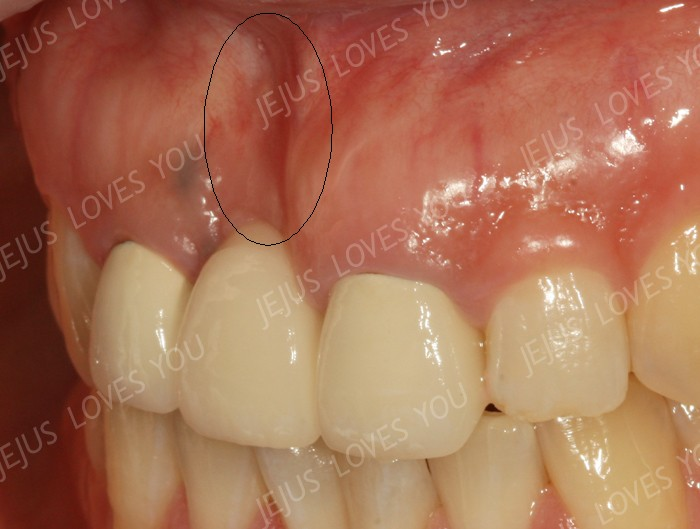

뼈이식/잇몸이식이 필요한 경우

앞니는 뼈 두께가 얇아 함몰(꺼짐)이 생기기 쉬운 부위입니다. 필요한 경우 초기부터 뼈이식과 잇몸이식을 함께 계획해야 자연스러운 잇몸 라인을 만들 가능성이 높아집니다.